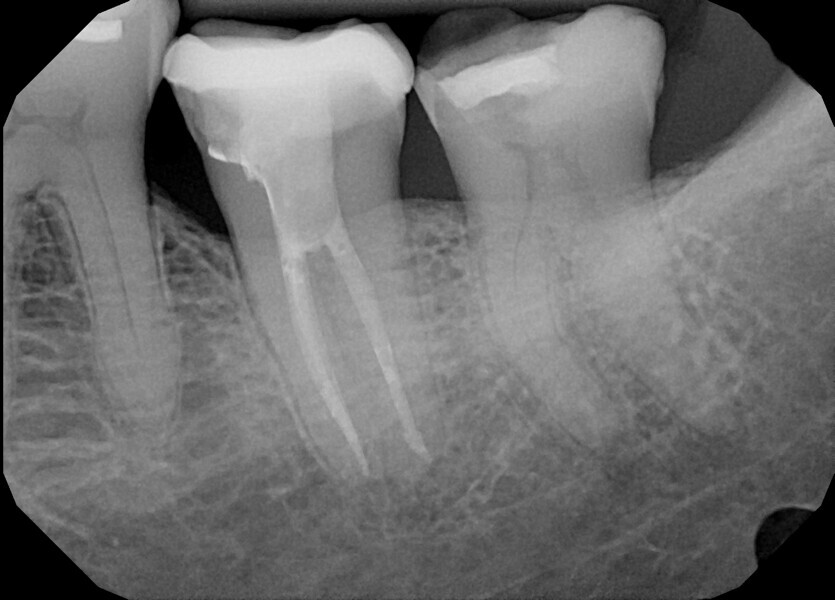

During the consultation appointment, a CBCT scan was performed. It revealed a small osteolytic lesion around the mesial root, suggesting the possibility of achieving patency in the root canals in the mesial root. Around the distal root, there were no signs of the lesion, which indicated that the mesial root was the cause of the symptoms. The radiographic examination also revealed a broken lentulo in the MB canal (Fig. 16).

Figs. 16 a & b